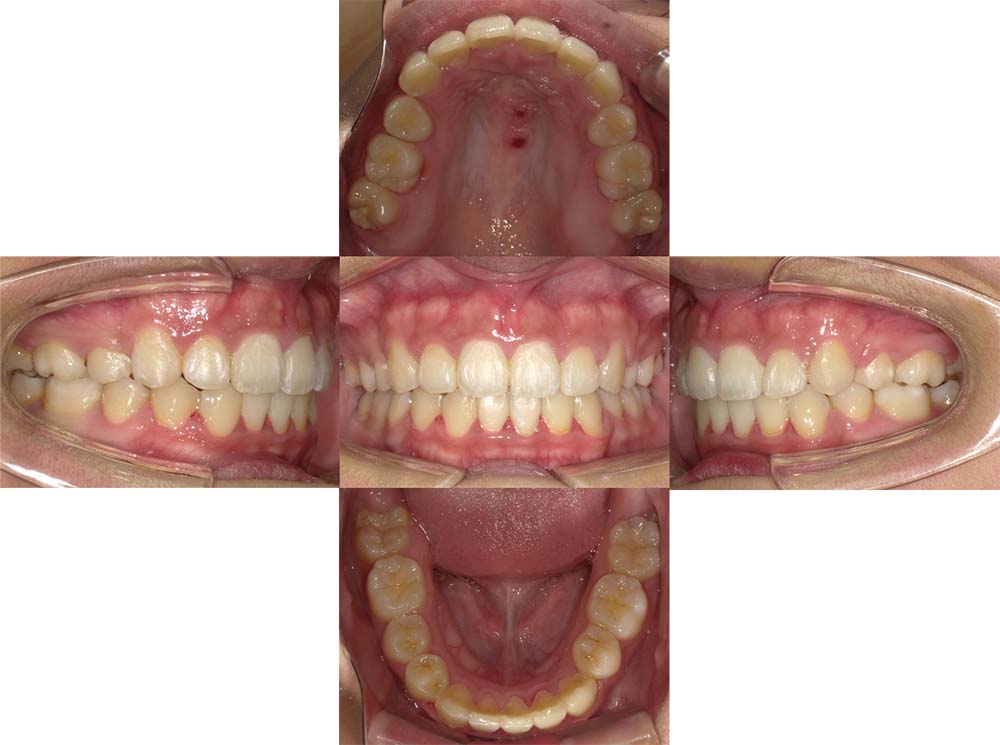

症例04

| 主訴 | 歯並びのガタガタと出っ歯が気になる。 |

| 診断名あるいは主な症状 | 上顎前突、叢生 |

| 年齢/性別 | 16歳・女性 |

| 矯正ステージ | 大人の矯正治療 |

| 治療方法 | ワイヤー矯正 |

| 抜歯部位/抜歯有無 | 抜歯 |

| 治療内容 | 抜歯したスペースを使用し、ガタガタの改善と上下顎前歯を後退させた。 |

| 費用 |

85万円程度(2025.10時点の料金となります。) ※矯正基本料金、審美ブラケットを含む |

| 治療期間 | 2年5ヶ月 |

| 主なリスク・副作用 | 痛み、歯根吸収、歯肉退縮、虫歯、後戻り |